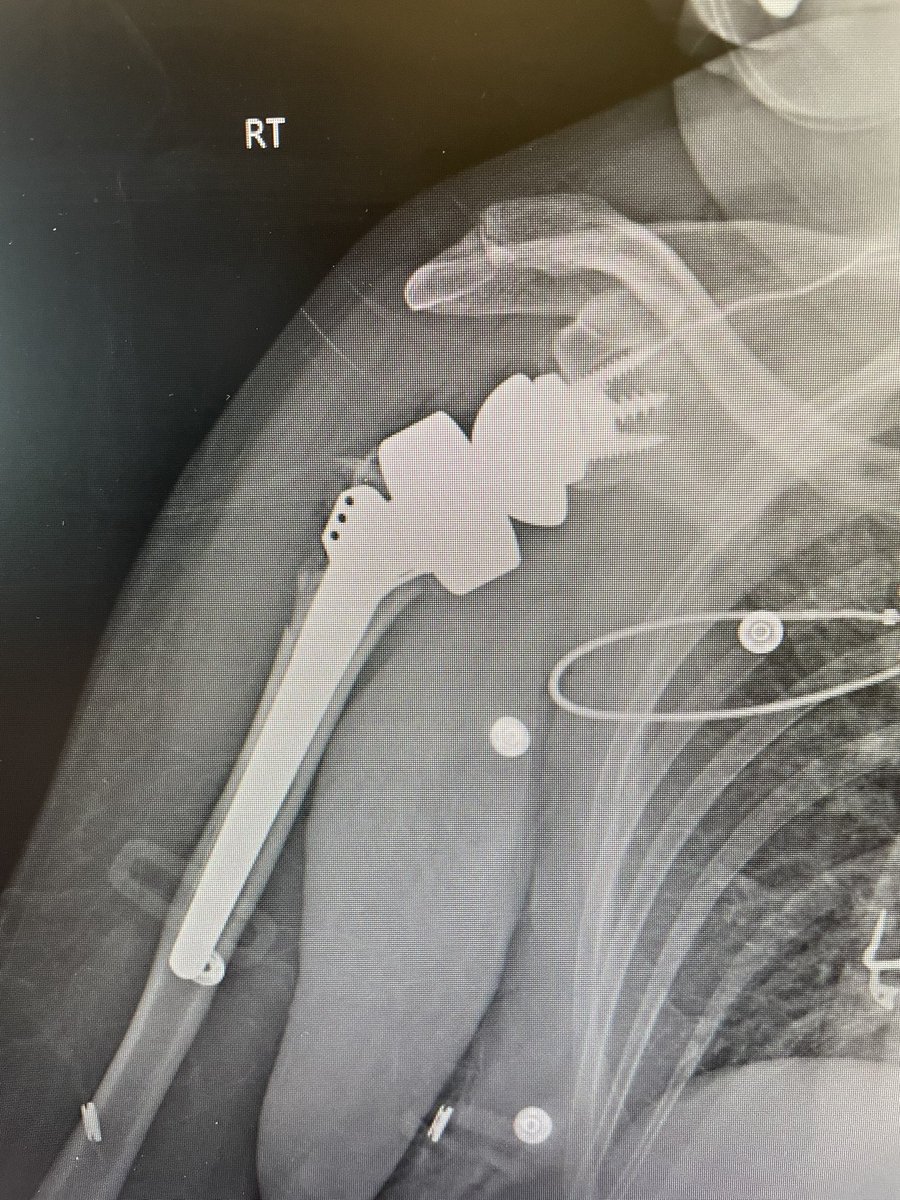

Incredibly excited to officially start my practice as a Shoulder and Elbow Surgeon at @DMC_Heals! Looking forward to seeing patients in Detroit, Dearborn, and Warren.

Orthopaedic Shoulder & Elbow Surgeon at Detroit Medical Center (Detroit, Dearborn, Sterling Heights). Team Physician for Detroit City FC. Opinions are my own.